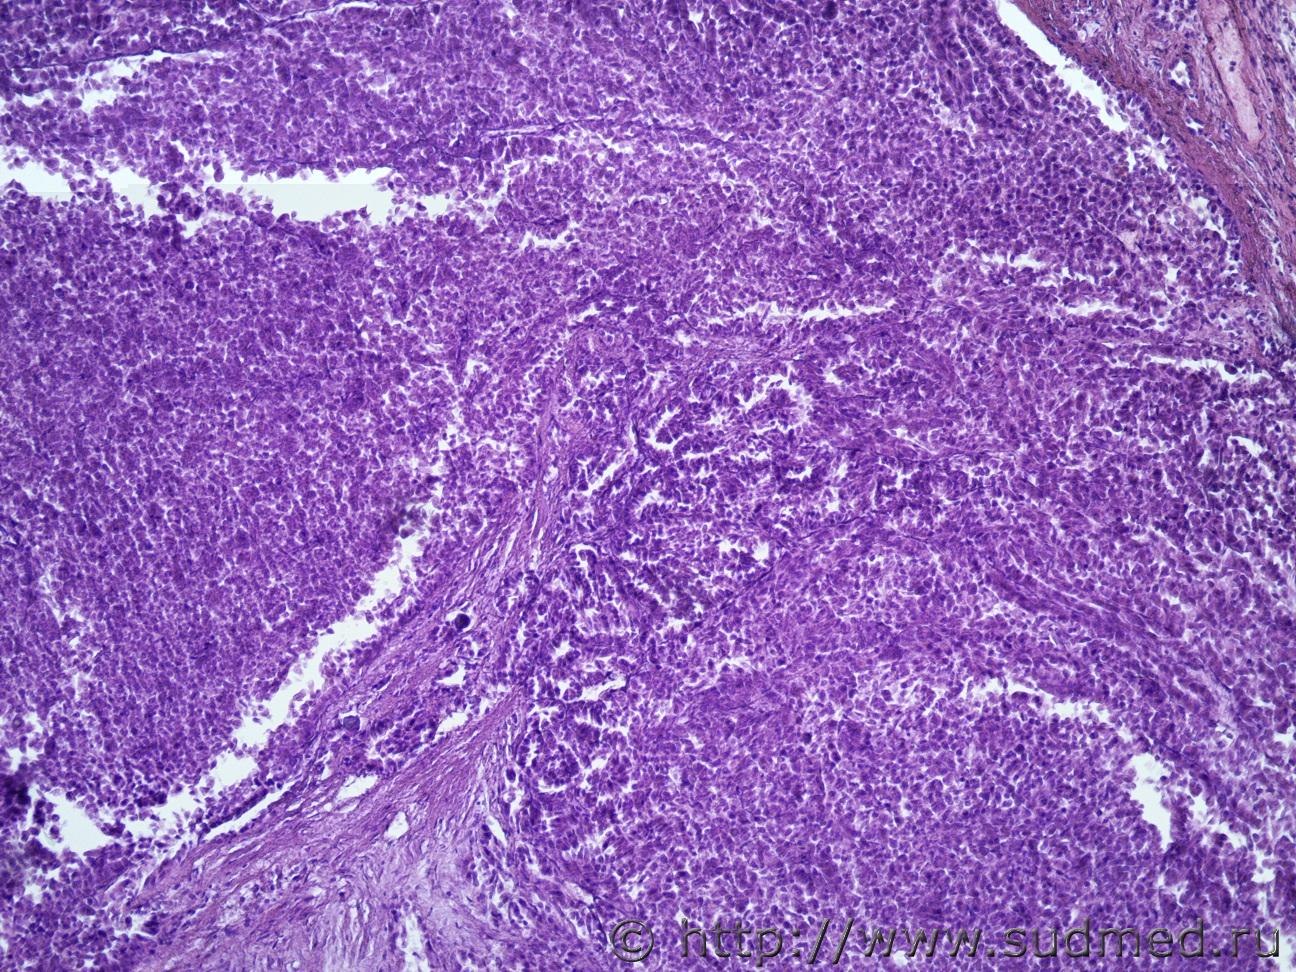

Жен 62 года. На задней поверхности левой почки желтовато-сероватый участок 1на1 см, творожистой консистенции.Судебная медицина - Прикрепленное изображение Судебная медицина - Прикрепленное изображениеСудебная медицина - Прикрепленное изображениеСудебная медицина - Прикрепленное изображениеСудебная медицина - Прикрепленное изображение

Почечноклеточный рак,другого не придумал. wink.gif

Меня тоже посещает мысль, что это почечно-клеточный рак, папиллярный тип)))